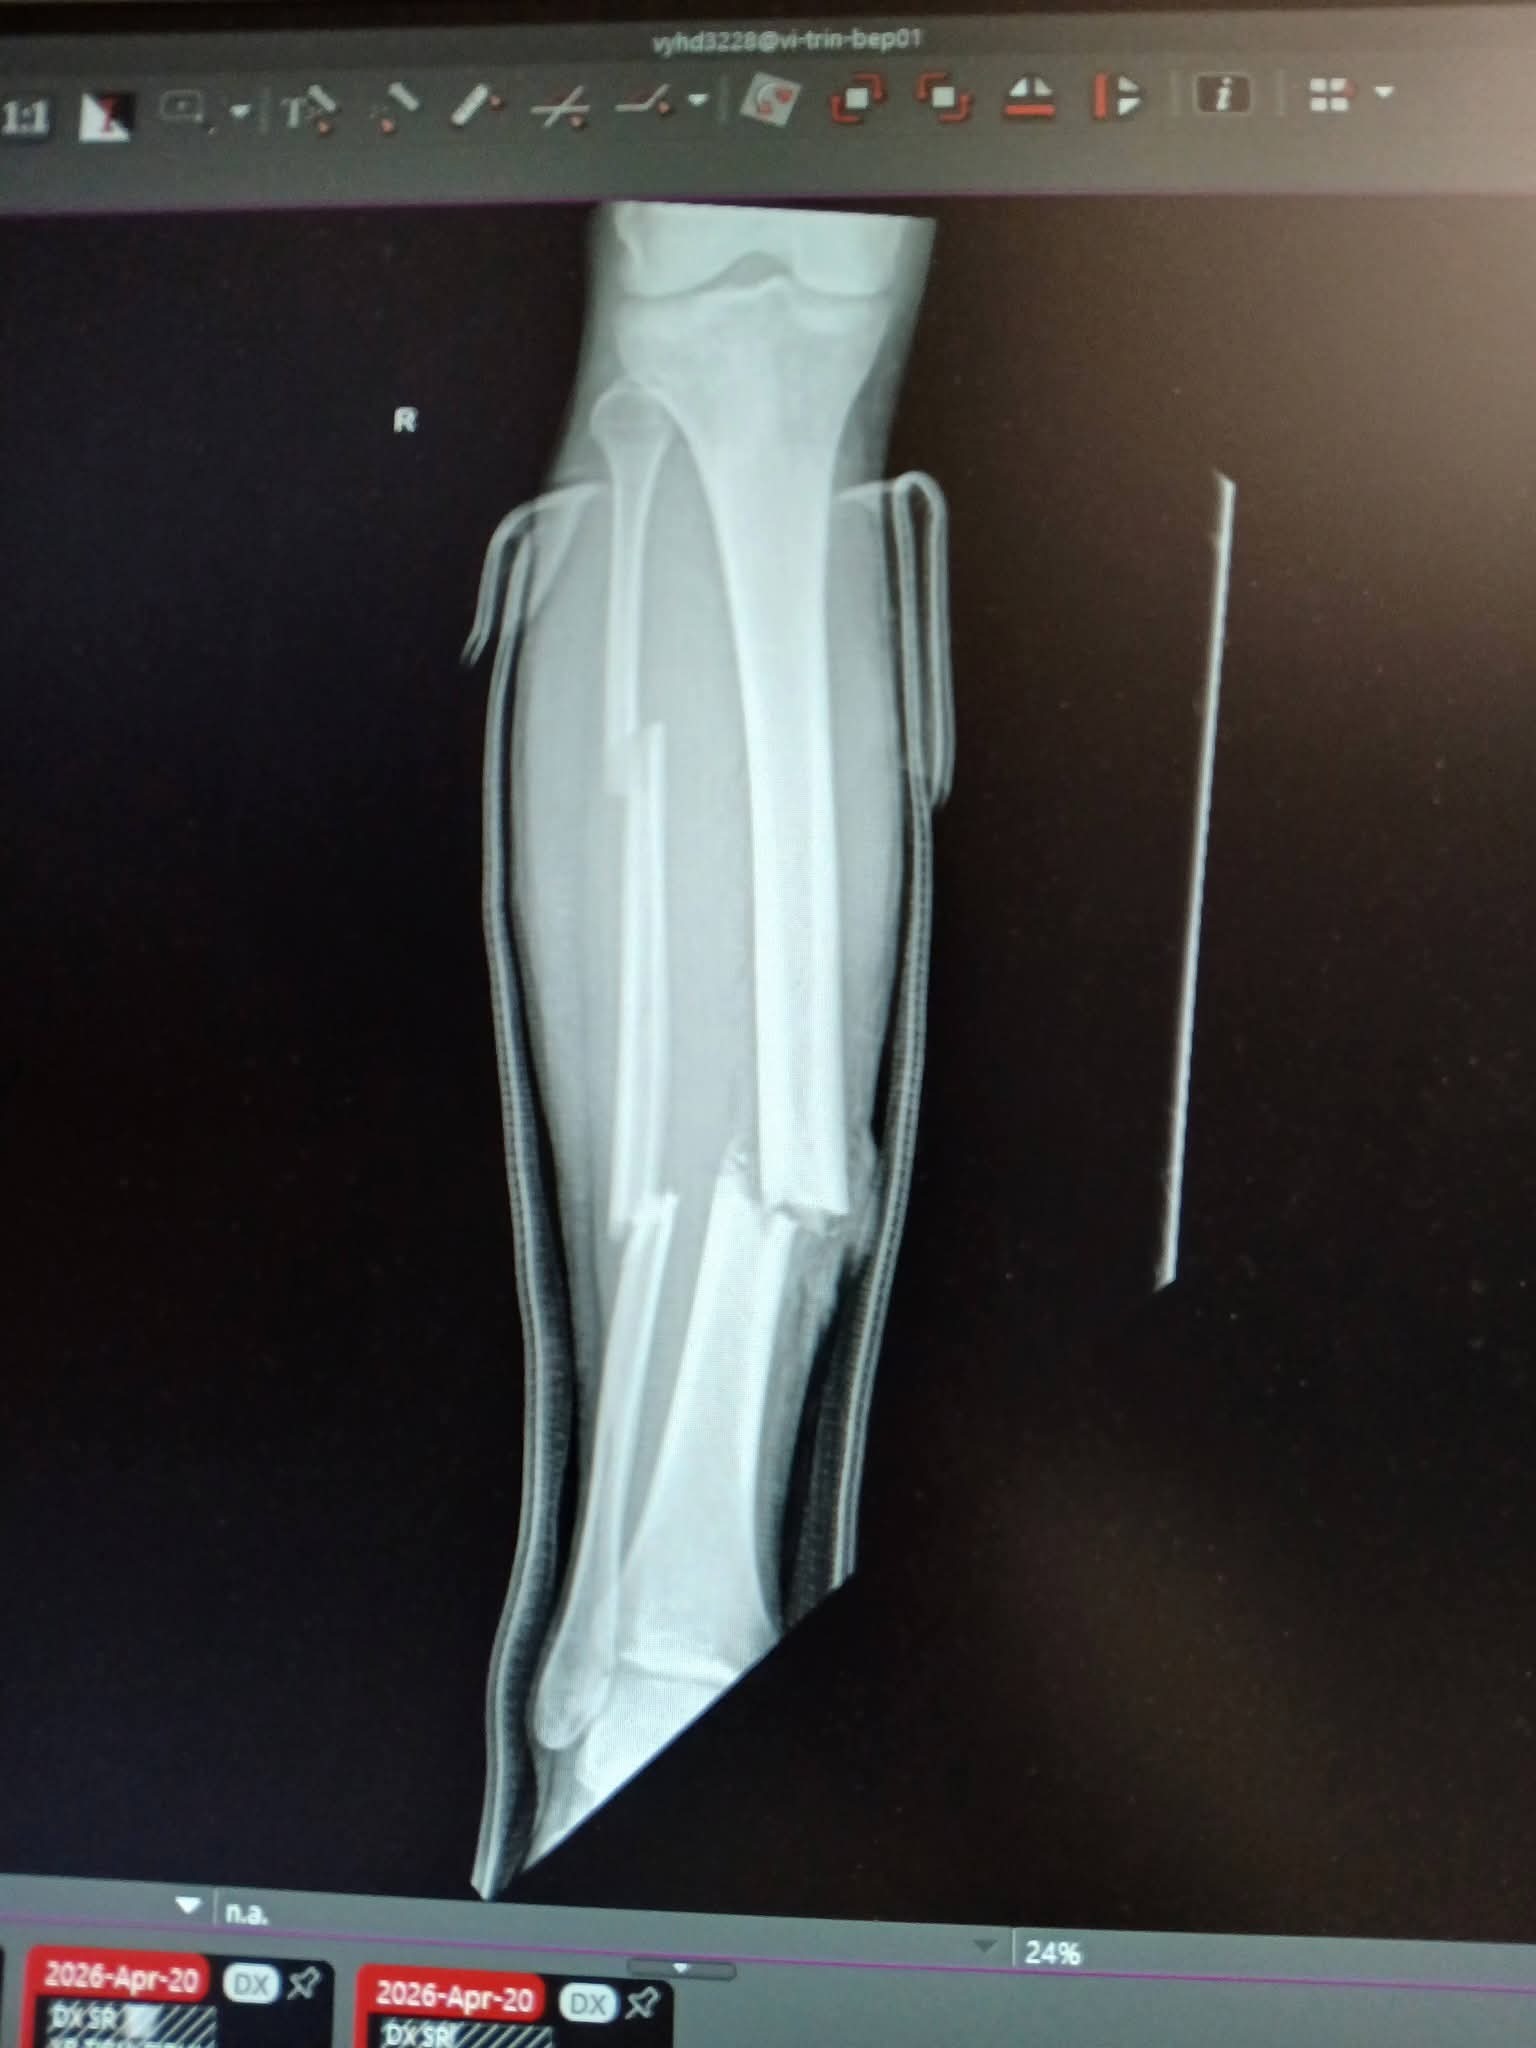

As some may have already heard, my boyfriend Nat was in a horrible motorcycle accident on Monday April 20th. He is going to have a long road to recovery with his leg broken in three places, a fractured rib, small fracture in his spine, a fractured wrist, abrasions on his lungs, and an AC ligament tear in his shoulder and rotator cuff. He has already been through one surgery on his leg, with a possible future surgery depending on how everything heals, as it is considered a high risk recovery and can have complications.